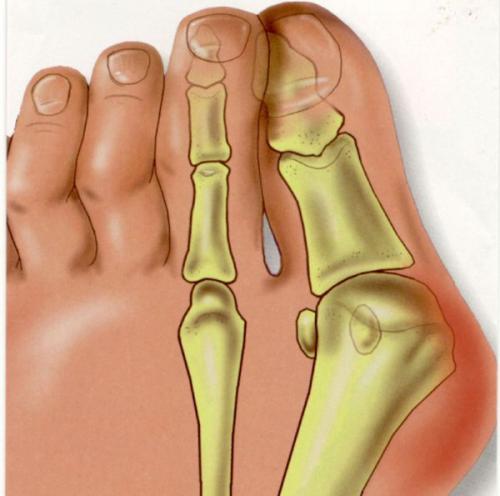

Вальгусное отклонение первого пальца — прогрессирующее дистрофическое заболевание стопы, при котором большой палец отклоняется наружу, а в области его сустава образуется экзостоз или "шишка". Помимо косметического дефекта, деформация приводит к нарушению ходьбы, вызывает боль и часто требует хирургического вмешательства. Пациенты с патологией не могут носить обычную обувь, а на тяжёлых стадиях — и ортопедическую. Это приводит к снижению подвижности и нарушению психологического равновесия больного.

Вальгусное отклонение большого пальца составляет более 70 % от всех ортопедических патологий. Заболеванием в 95 % случаев страдают женщины. Нарушение возникает после 30-40 лет и вызвано гормональными изменениями : яичники вырабатывают меньше половых гормонов — эстрогенов, оказывающих защитное воздействие на соединительную ткань. Соединительная ткань непрерывно обновляется, подвергается перестройке в ответ на нагрузку и повреждение. Структурным компонентом соединительной ткани являются коллагеновые волокна. Основная функция коллагена заключается в том, чтобы придавать соединительной ткани прочность и долговечность. Дефицит эстрогенов ведет к снижению образования коллагена в соединительной ткани. В результате капсульно-связочная система, состоящая из соединительной ткани, теряет прочность.

Основным фактором, способствующим развитию деформации стопы, является ношение неудобной обуви — узкой и на каблуке более трёх-четырёх сантиметров. Усугубить патологию может беременность, продольное плоскостопие, травмы стопы и голени.